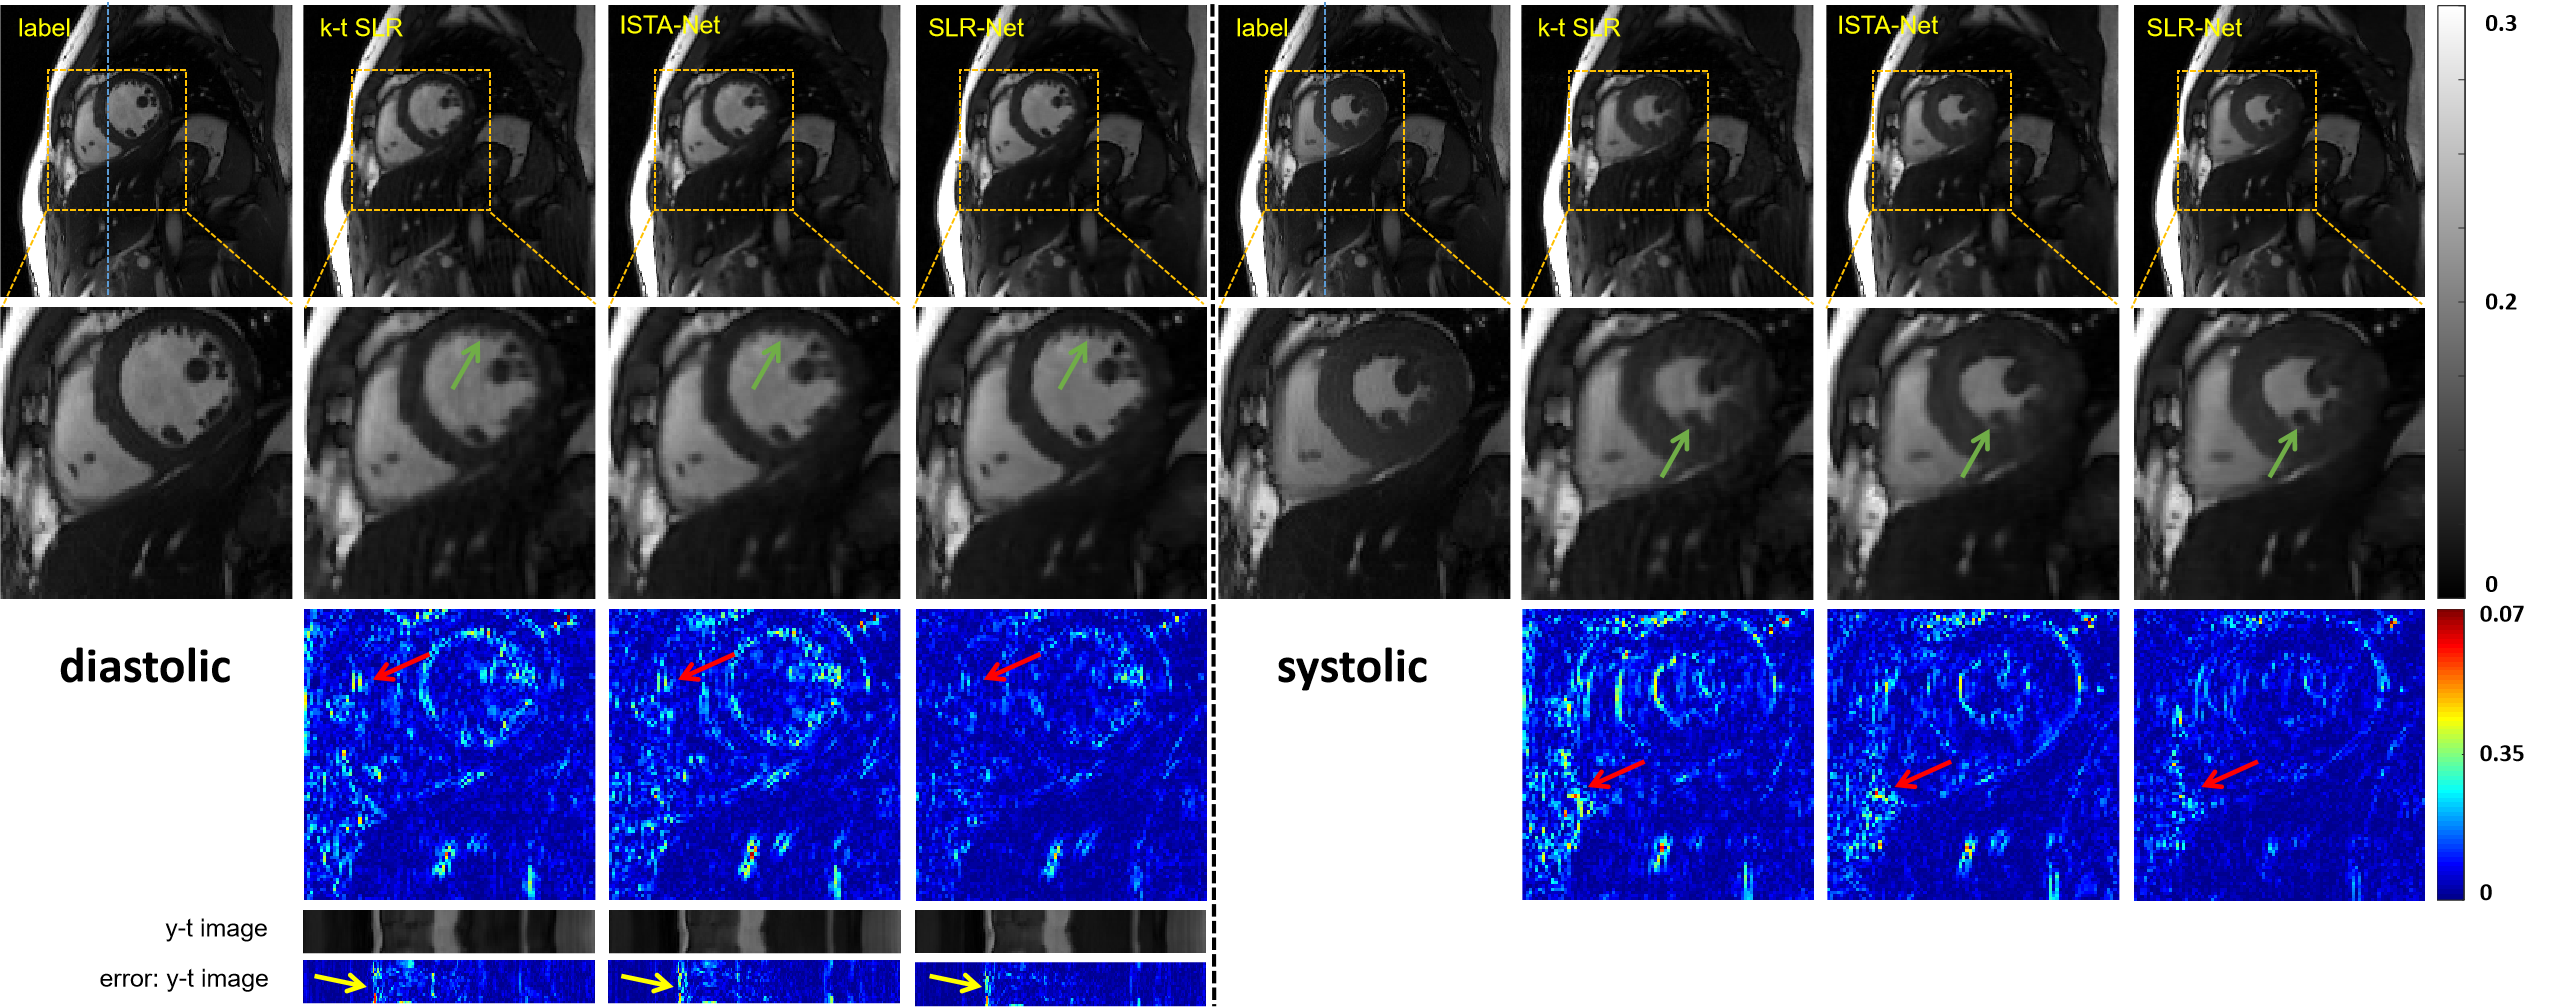

III-B The Reconstruction Performance of the Proposed SLR-Net

To demonstrate the efficacy of the proposed deep unrolling method, we compared it with a state-of-the-art CS-LR method k-t SLR [16] and a sparse-based CNN method ISTA-Net [22]. The reconstruction results of these methods at 8-fold acceleration are shown in Fig.4. We present both diastolic and systolic reconstruction results to demonstrate the performance of different heart phases. The left half shows diastolic reconstruction results, and the right half shows systolic reconstruction results. The first row shows, from left to right, the ground truth and the reconstruction result of these methods. The second row shows the enlarged view of their respective heart regions framed by a yellow box. The third row shows the error map (display ranges [0, 0.07]). The y-t image (extraction of the 124th slice along the y and temporal dimensions) and the error of y-t image are also given for each signal to show the reconstruction performance in the temporal dimension. The reconstruction performance of the two deep learning based methods (ISTA-Net and SLR-Net) is better than that of the traditional iterative method (k-t SLR), which can be clearly seen from the error maps. The comparison between the two deep learning methods shows that SLR-Net is better than ISTA-Net in both detail retention and artifact removal (as shown by the green and red arrows). This indicates that the deep low-rank prior plays an important role in dynamic MR reconstruction. The y-t results also have consistent conclusions, as shown by the yellow arrows.

We also provided quantitative evaluations in Table I. One can see that the SLR-Net achieves optimal quantitative evaluations. Although the introduction of deep low-rank increases the amount of computation, the effect on the reconstruction time is very small and can even be ignored compared with the reconstruction time of k-t SLR. In both qualitative and quantitative results, we can draw a conclusion: the first scheme of deep low-rank prior, an unrolling sparse and low-rank network, can effectively explore the low-rank prior of dynamic data, thus improving the reconstruction performance.